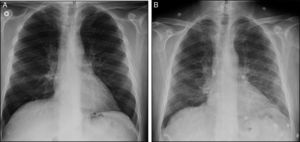

Case ReportThe patient was a 61-year-old man with a personal history of asthma who was diagnosed with AOSD in October 2011. He was initially treated with nonsteroidal anti-inflammatory drugs (NSAID). After 1 month, glucocorticoid (GC) therapy was started because of the development of skin involvement. In March 2012, subcutaneous methotrexate (MTX) was added as a steroid-sparing agent, and was escalated up to 25mg a week. For 2 years, a good control of the disease was achieved and maintained, making it possible to reduce the prednisone dose to 2.5mg/day. However, in November 2014, the patient experienced a severe joint and cutaneous flare that required hospital admission and an increase in corticosteroid therapy. After 1 month, the decision was made to initiate treatment with tocilizumab (TCZ) because of persistent arthralgia, fever and neutrophilic leukocytosis with hyperferritinemia, despite the treatment with MTX and high-dose oral GC. Three weeks after receiving the first and only dose of TCZ at 8mg/kg body weight, he presented to the outpatient clinic with dyspnea on moderate exertion. There was no evidence of infection or cardiac decompensation. The only noteworthy finding on physical examination was a baseline oxygen saturation (SO2) of 93%. An emergency chest radiograph (Fig. 1A) showed a faint image of bilateral interstitial involvement and the patient was referred to the emergency department. The results of the laboratory analyses performed there included a slightly decreased partial pressure of oxygen (PO2) (70.900mmHg), leukocytosis (13.54×103/μL), neutrophilia (11.93×103/μL), lymphopenia (0.59×103/μL), C-reactive protein < 0.5mg/L and elevated D-dimer (1.77μg/mL). The electrocardiogram was normal. Computed tomography (CT) angiography served to rule out pulmonary thromboembolism. However, the lung window (Fig. 2) revealed an increased ground glass density, predominantly in middle and upper lobes, suggestive of alveolar inflammation. In agreement with the pulmonology department, and given that the clinical signs were mild at that time, the decision was made to carry out pulmonary function tests (PFT), to perform a clinical reevaluation over the following days and to discontinue treatment with MTX and TCZ, as we suspected their possible implication in this condition. He returned 2 days later, complaining of a significant deterioration in his clinical status, with the development of fever and a dry cough, and was unable to complete the scheduled PFT. On the other hand, he had been taking amoxicillin/clavulanic acid for the preceding 2 days because of a dental abscess. A chest radiograph performed at that time (Fig. 1B) showed an increase in diffuse density in the region of the hilum and base of the lung. He was admitted to the hospital to complete the study and begin treatment with prednisone at 30mg/day. The laboratory tests revealed a ferritin level of 4023ng/mL (previously 1997ng/mL), C-reactive protein at 17.7mg/L, leukocytosis at 15,280×103/μL, neutrophils at 12,360×103/μL and lymphocytes at 1870×103/μL, there being no other noteworthy findings. Bronchoalveolar lavage revealed an increase in the percentage of lymphocytes, with normal lymphocyte subsets and negative results for cytology and cultures for fungi, cytomegalovirus, herpes, influenza/parainfluenza and adenovirus, and negative staining of acid-alcohol fast bacilli. The PFT disclosed a restrictive change with a reduced diffusing capacity (48%), which was not corrected for at alveolar volume. During his hospital stay, the patient initially required oxygen therapy at 1.5bpm and, subsequently, treatment with subcutaneous anakinra was introduced at 100mg/day. Within a few days, he began to show progressive improvement in both clinical signs and laboratory results, as well as normalization of the radiographic pattern after 10 days and, after 1 month, control of ferritin and CT images.